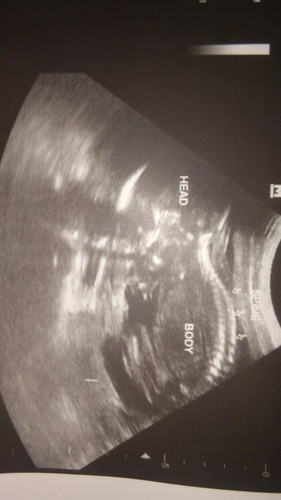

hi Mamies.. just asking.. How do we know if the baby is a girl or boy.. i have my ultrasound last week . . but the pelvic ultrasound can detect the gender of my baby bcouse my Lo is not her/him on the position??.. (breed position ata tawag dun..)

Parang girl mommy hehe

pano nio po nalman?? na girl baby ko?